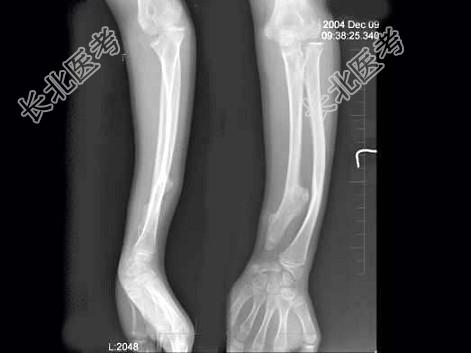

- 单项选择题女,12岁, 左前臂外翻畸形4年,摄片如图所示, 最可能的诊断是 ( )

A、奥利氏病

B、马德隆氏畸形

C、先天性干骺端发育不全

D、软骨发育不全

E、以上均不正确